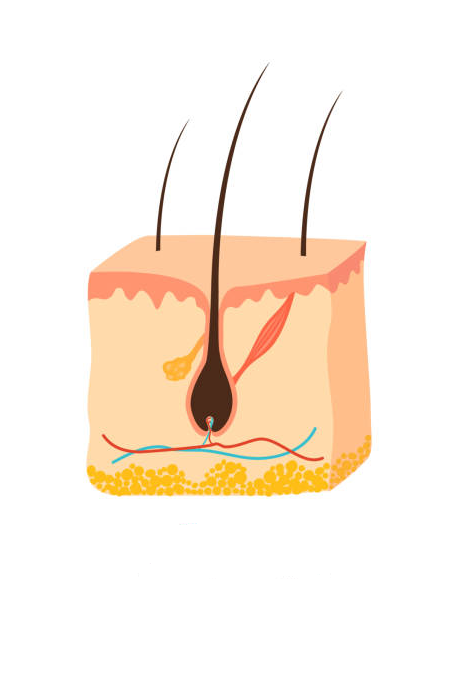

CONNECT WITH CONNECTIVE TISSUE